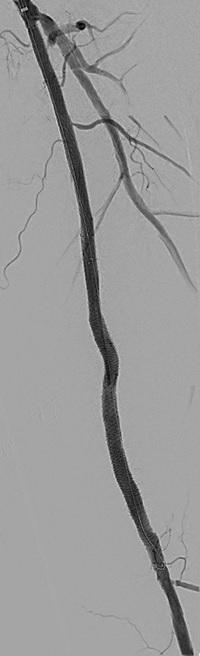

n PERIPHERAL ARTERIAL DISEASE:

Crossing chronic total occlusion lesions are challenging procedures. The BeBack crossing catheter—Bentley’s first product to be available in both Europe and the USA following the company’s acquisition of Upstream Peripheral Medical Technologies’ GoBack crossing catheter in September 2022— offers a new solution in this space. In a Bentleysponsored advertorial, Andrej Schmidt (Leipzig, Germany) shares his clinical experience with the BeBack, noting how it has been a “gamechanger” in his endovascular peripheral arterial disease practice.

For more on this story go to page 19.